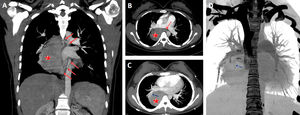

A 18-year-old female presented for evaluation of recurrent cough and hemoptysis. A giant pulmonary sequestration mimicking a paravertebral mass was detected in computed tomography (Fig. 1A–D).

Coronal (A) and axial (B) CT scans show a giant pulmonary sequestration (star) feeding by systemic arteries (red arrows). Maximum intensity projection (MIP) axial CT scan (C) also reveals that the pulmonary sequestration was drained by the pulmonary vein (blue arrow) of the right lower lobe. Coronal volume rendering negative MIP image shows clearly the drainage vein (blue arrow). RPA, right main pulmonary artery; RPV, right main pulmonary vein.

Pulmonary sequestration is a rare congenital lung anomaly. It is defined by nonfunctional lung tissue originating from the normal bronchopulmonary system and bleeding from the aberrant systemic artery. Pulmonary sequestration is classified as extralobar and intralobar. About three quarters of the cases are localized in the left lower lobe. In rare cases, it can mimic a benign or malign thoracic lesions.1,2 Detecting pulmonary sequestration before surgery is very important to prevent serious intraoperative complications.